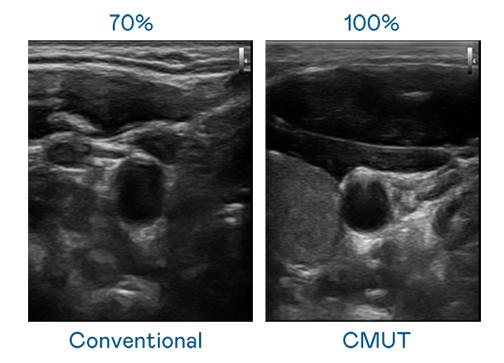

CMUT 技術是一種用電容式微機電元件來產生超音波訊號的技術。與傳統 PZT 壓電式技術相比,CMUT 頻寬增加 30%,更寬頻的超音波訊號讓影像解析度大幅提升,是實現高影像品質醫療超音波掃描、促進精準醫療發展的關鍵技術。

超音波影像的解析度高低,首先取決於探頭能發出的訊號頻寬。BC贷 CMUT 可提供高清晰的超音波訊號,提供高頻寬、高靈敏度、影像紋理細節更高的超音波影像,協助醫護人員縮短影像判讀時間及利用精準的醫療影像進行診斷。